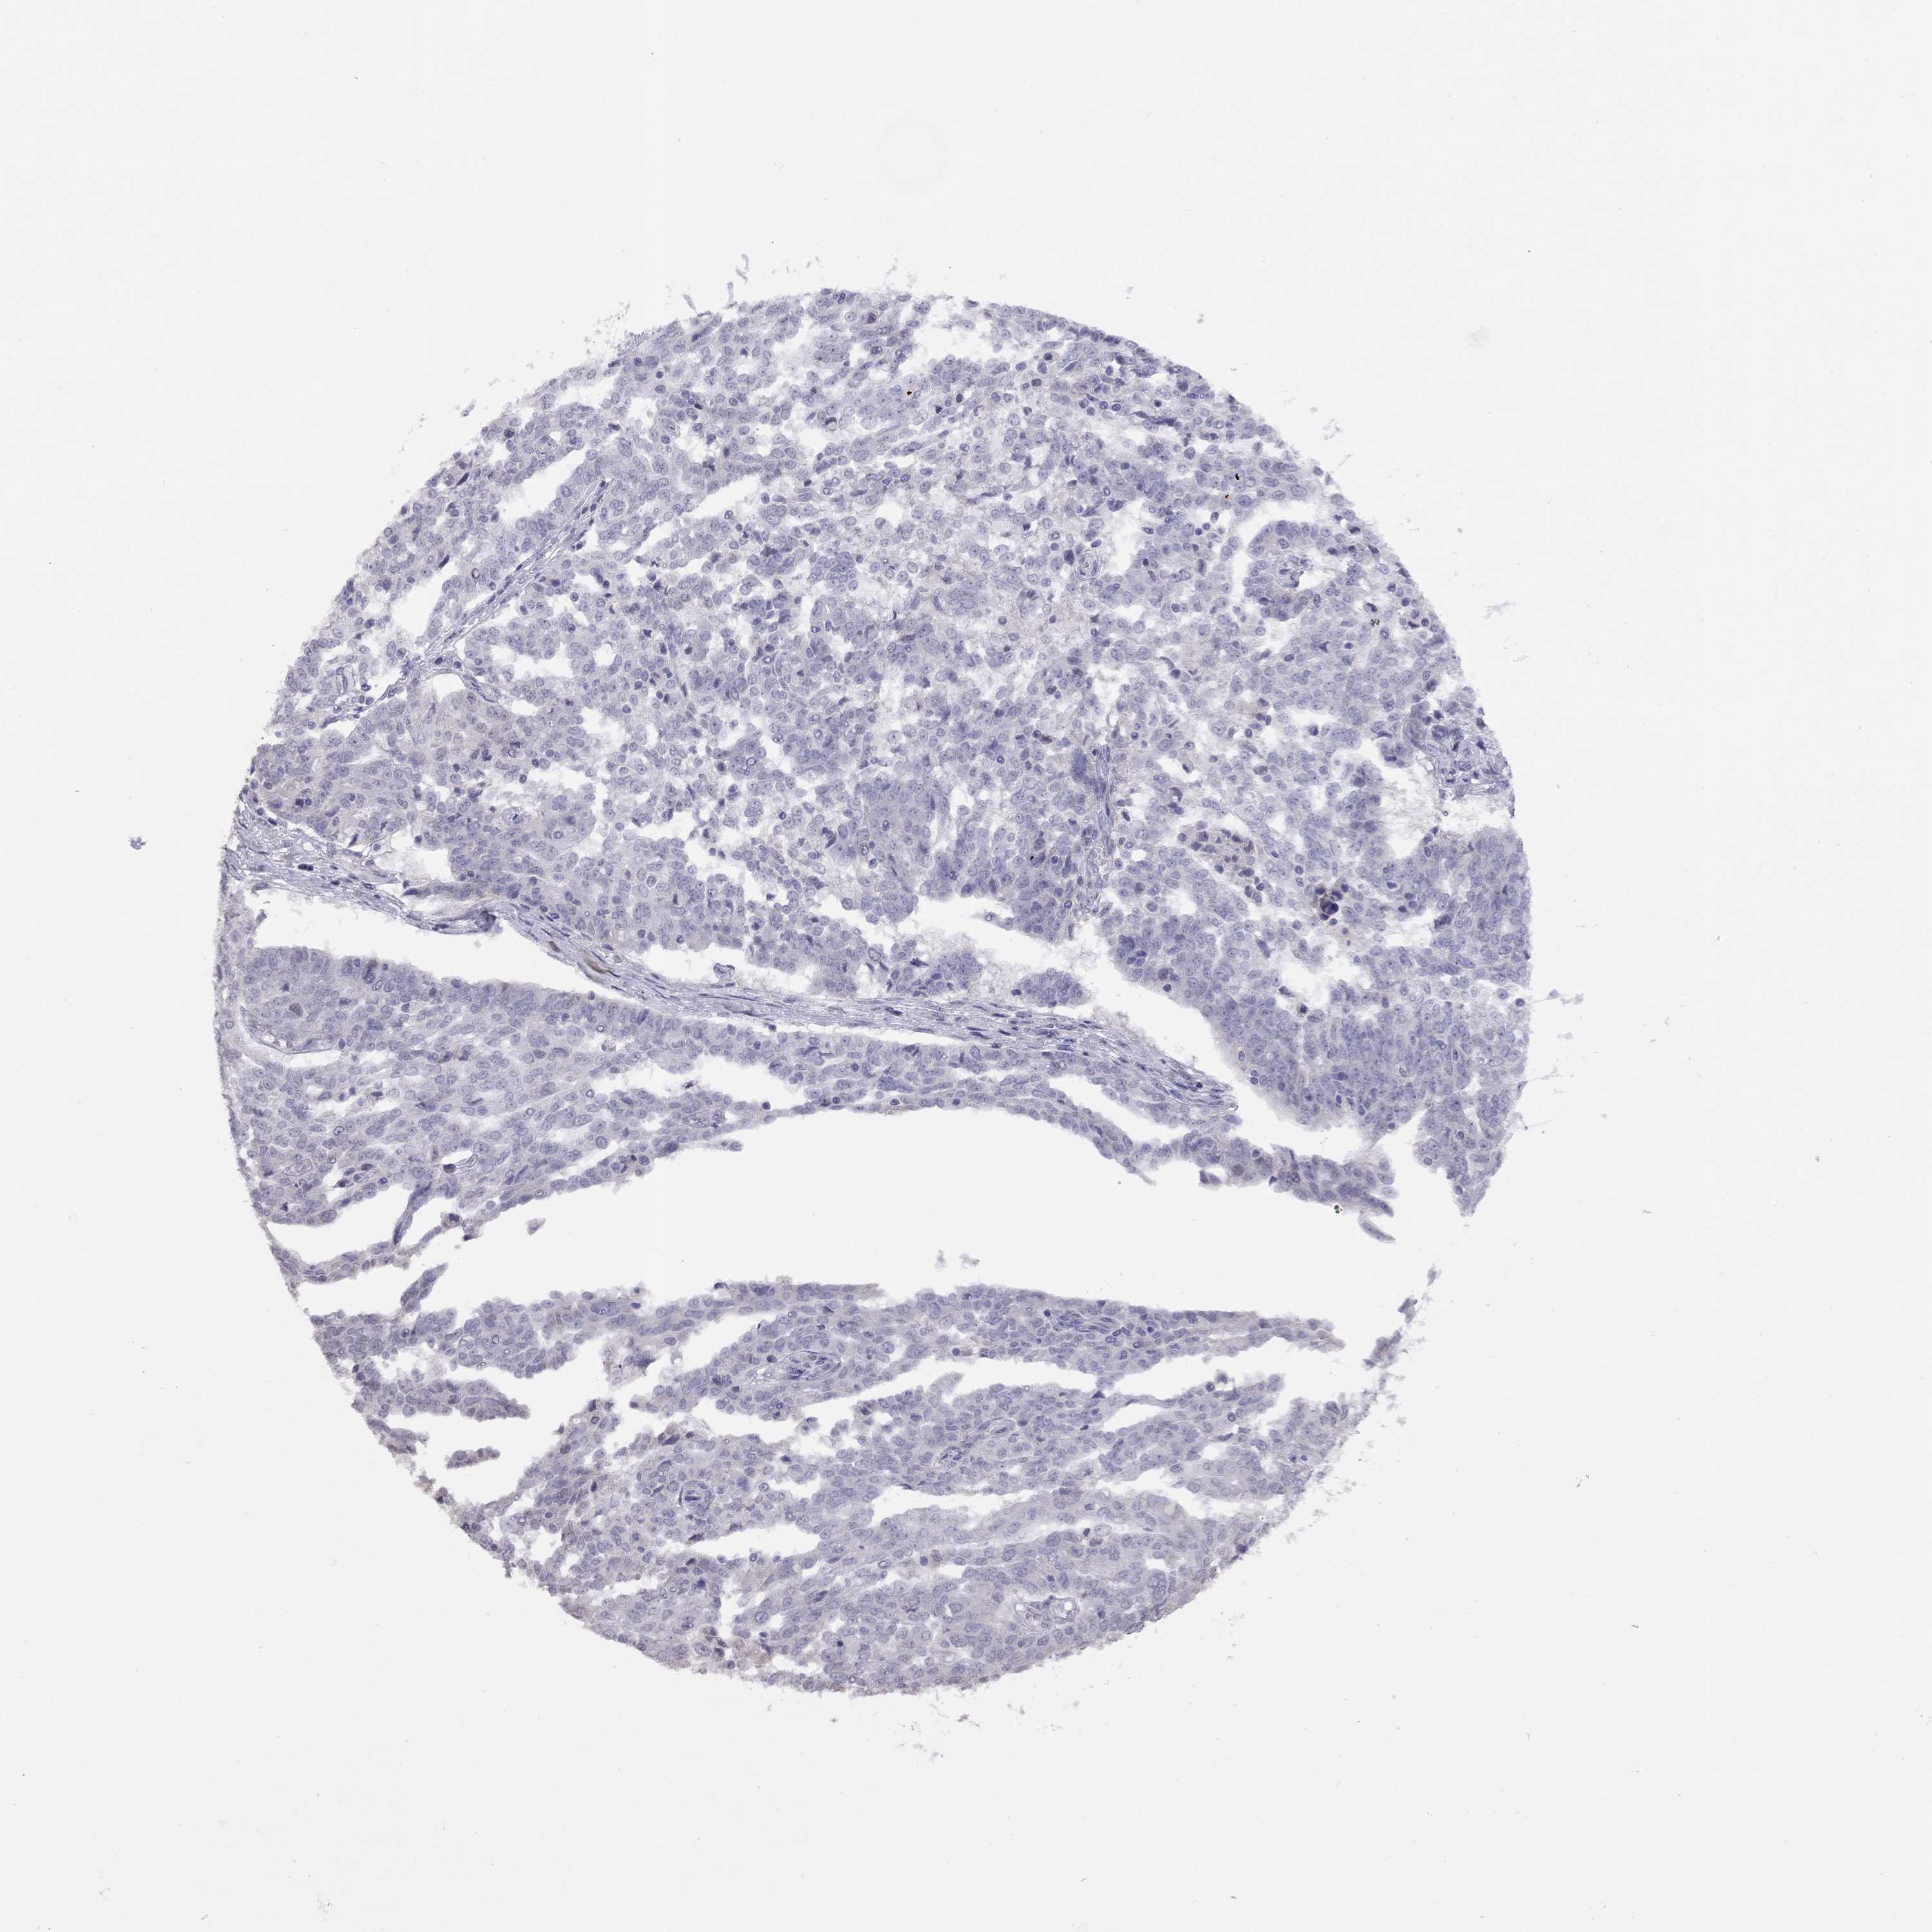

OVARIAN CANCER - Protein expressioni

A mouse-over function shows sample information and annotation data. Click on an image to view it in a full screen mode. Samples can be filtered based on level of antibody staining by selecting one or several of the following categories: high, medium, low and not detected. The assay and annotation is described here.

Note that samples used for immunohistochemistry by the Human Protein Atlas do not correspond to samples in the TCGA dataset.

Antibody stainingi

Antibody staining in the annotated cell types in the current human tissue is reported as not detected, low, medium, or high, based on conventional immunohistochemistry profiling in selected tissues. This score is based on the combination of the staining intensity and fraction of stained cells.

Each image is clickable and will lead to virtual microscopy that enables deeper exploration of all samples and also displays staining intensity scores, fraction scores and subcellular localization as well as patient and tissue information for each sample.

Antibody HPA076164

Staining

High

Medium

Low

Not detected

Intensity

Strong

Moderate

Weak

Negative

Quantity

>75%

75%-25%

<25%

None

Location

Nuclear

Cytoplasmic/membranous

Cytoplasmic/membranous,nuclear

Cystadenocarcinoma, serous, NOS